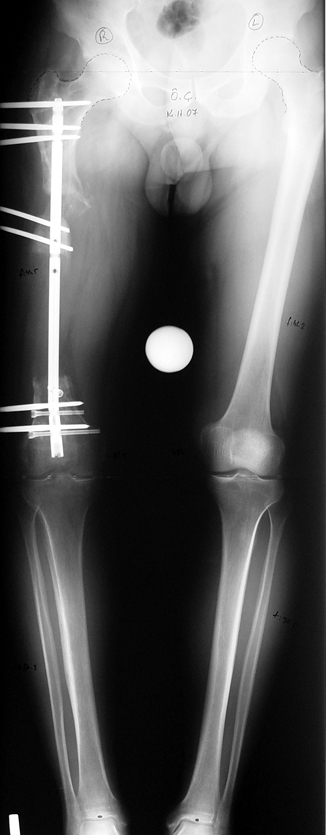

Appropriate radical debridement necessitates excision of all necrotic bone and soft tissues, and frequently causes instability at the involved extremity. The remaining bone and soft tissue defect has to be fixed and reconstructed. The distraction osteogenesis method of Ilizarov is used successfully for achievement of union, correction of the deformity, elimination of limb length inequality and reconstruction of segmental bone defects.

The duration of external fixation (external fixation index) depends on the amount of distraction required, and the extremity is prone to complications during this period. After the distraction phase is completed, the external fixator remains in place during the consolidation phase, which lasts twice as long as the distraction phase; but this period is hardly tolerated. If the external fixator is removed before sufficient consolidation is achieved, fractures, deformity and shortness will be the result. In our department, ‘lenghthening over nail’ method is used in order to decrease the external fixation index and increase patient comfort and activity level. In this method, the intramedullary nail is statically locked after the completion of the distraction phase, and external fixator is removed. The extremity is stabilized by the intramedullary nail during consolidation phase. In this way, complications due to long external fixation index or early removal of the external fixator are avoided.

Case 2